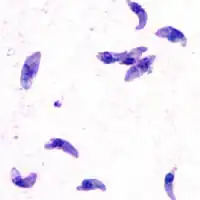

T. gondii is an apicomplexan parasite that can cause infection in humans. The parasite can live in many mammals and birds, but it carries out the sexual part of its lifecycle in cats. Feline feces from infected cats or undercooked meat from infected livestock contain T. gondii oocysts. Ingesting these could lead to toxoplasmosis, a disease which at its worst can cause encephalitis or miscarriage as the disease is passed from mother to fetus.

T. gondii and other apicomplexan parasites rely on actin-dependent gliding motility in order to gain access to the body. This form of cellular motion requires profilin, an actin filament binding protein that helps restructure the actin cytoskeleton. Without profilin, T. gondii can still grow and replicate, but it loses the ability to pass through cell layers and biological barriers in order to carry out infection. Thus profilin is a conserved, essential protein for T. gondii infection efficacy.[12]